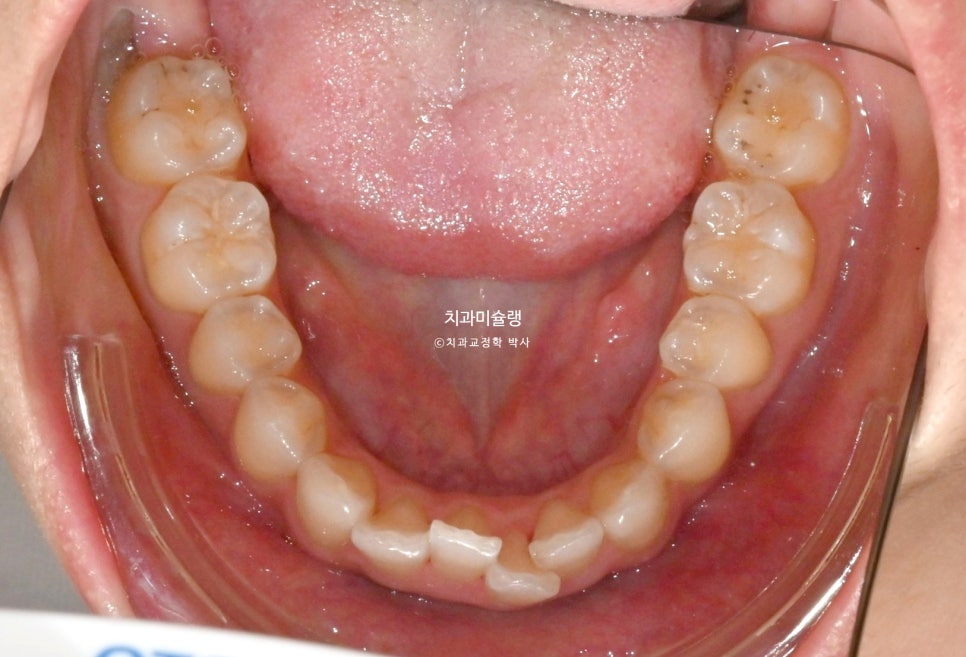

작년 여름, 교정치료를 위해 내원한 환자분 입니다.

앞니가 삐뚤하며 치축이 기울어져 있고 중심선이 약간 어긋나 있습니다.

그에비하면 어금니는 교합이나 배열이 좋은편입니다.

이 케이스는 앞니에 치아가 겹쳐진 부분이 펴지면서 블랙트라이앵글 발생이 예상됩니다.

아이테로 구강스캐너로 스캔을 한후 배열후 모습을 확인할 수 있는데, 이 과정에서 보이는 블랙트라이앵글의 대략적인 사이즈와 부위를 미리 시각화해서 볼 수 있죠.